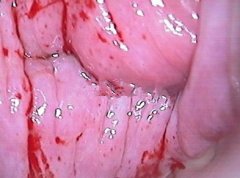

• 轻度宫颈炎图片-慢性宫颈炎的图片发布日期:2012-11-14 09:35:30

宫颈炎出血图片 轻度宫颈炎图片[详情]